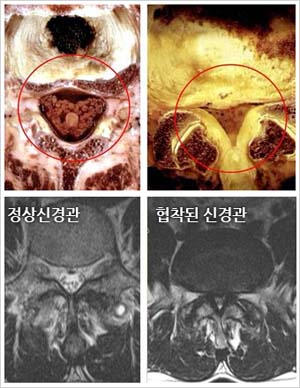

오늘 글에서는 척추관 협착증 증상 치료방법에 대해서 알아보도록 하겠어요. 척추관 협착증은 퇴행성 디스크와 아울러 전형적인 퇴행성 척추질환입니다. 척추의 퇴행이 오래 진행되어 인대가 두꺼워지고 붓게 된다면 신경구멍이 좁아지며 척추관 협착증이 유발되요.

허리 디스크와는차이나게 척추관 협착증은 요통보다는 다리 저림이나 당김 증상이 있어, 보행에 제일 큰 고충을 체감할 수 있습니다. 때문에 오래 걷기가 힘들고 오래 걷지 않았음에도 자꾸 주저앉게 되는 성향이 존재하는데 표준적인 협착증의 증상이라 할 수 있습니다. 기본적으로 요추부(허리)의 문제이긴 하지만 허리디스크와 다르게 허리 통증이 한결같이 동반되지는 않으며, 있더라도 허리디스크에 대조해서 적은 정도의 통증이 일어납니다.

척추관 협착증 환자는 협착된 척추관 부근에 염증이 발생하여 심각한 통증을 느끼게 되고, 두꺼워진 인대가 신경을 압박하게 되고요. 자생한방병원에서는 염증과 부기를 가라앉히는데 효과가 있는 디스크 치료 한약으로 협착으로 인해 유발된 통증을 감량시켜주며, 부서진 근처 연조직의 흠집를 낫게 하죠. 한약은 퇴행된 뼈의 재생을 증대시키고 두꺼워진 인대 근처의 염증을 가라앉히는 효과가 있어요. 자생에서는 이런 한약과 나란히 척추관을 벌려주는 추나요법 등을 같이 진행하여 척추관 협착증을 치료하죠.